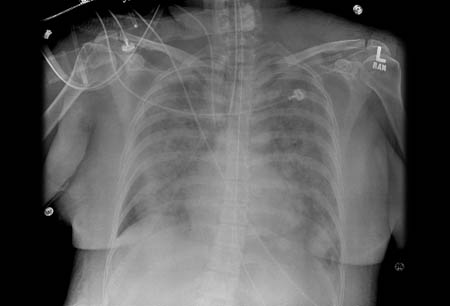

- chest x-ray